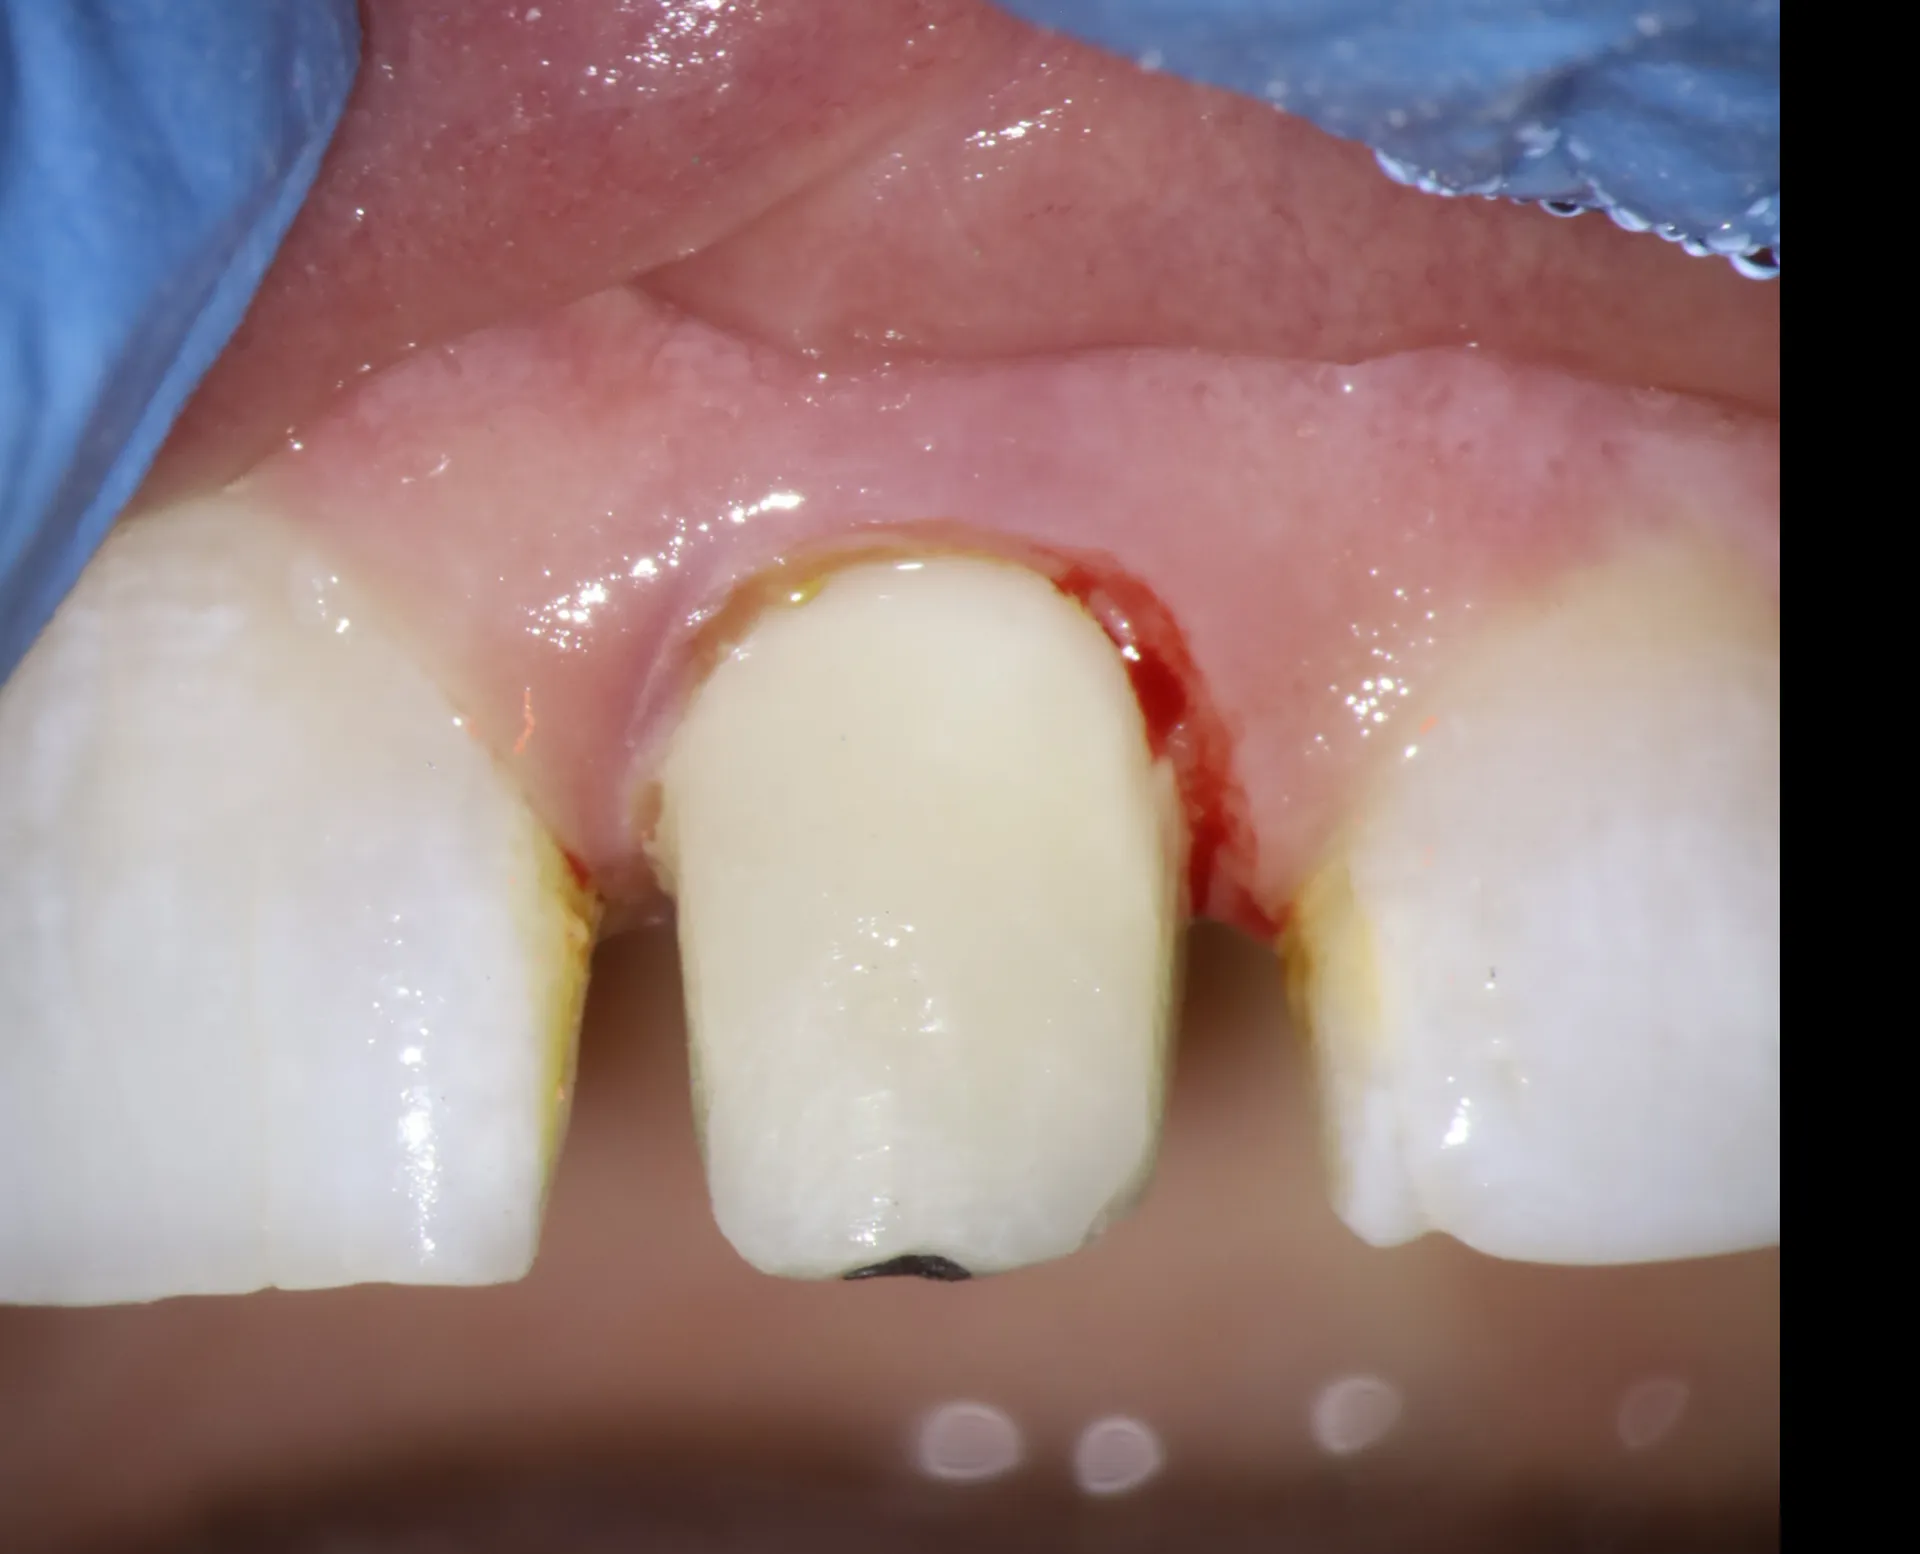

Phase 2: Fiber Post Placement (Minutes 60-75)

After achieving proper endodontic seal, intraradicular reinforcement was needed due to minimal remaining coronal structure:

• Post space preparation: Remove gutta-percha from coronal 2/3 of canal, leaving 4-5mm apical seal

• Post selection: Choose fiber post diameter matching prepared post space

• Post try-in: Verify post extends adequately into canal and provides sufficient length for core buildup

• Adhesive cementation: Bond fiber post using dual-cure resin cement with total-etch adhesive protocol

Phase 3: Composite Buildup (Minutes 75-90)

Final phase restored coronal tooth anatomy:

• Build composite core around fiber post using layering technique

• Restore anatomic contours to prepare for eventual crown

• Ensure adequate ferrule (2mm of sound tooth structure for crown margin)

• Refine margins and polish buildup

• Place temporary crown for protection and aesthetics

• Schedule with restorative dentist for definitive crown in 2-3 weeks